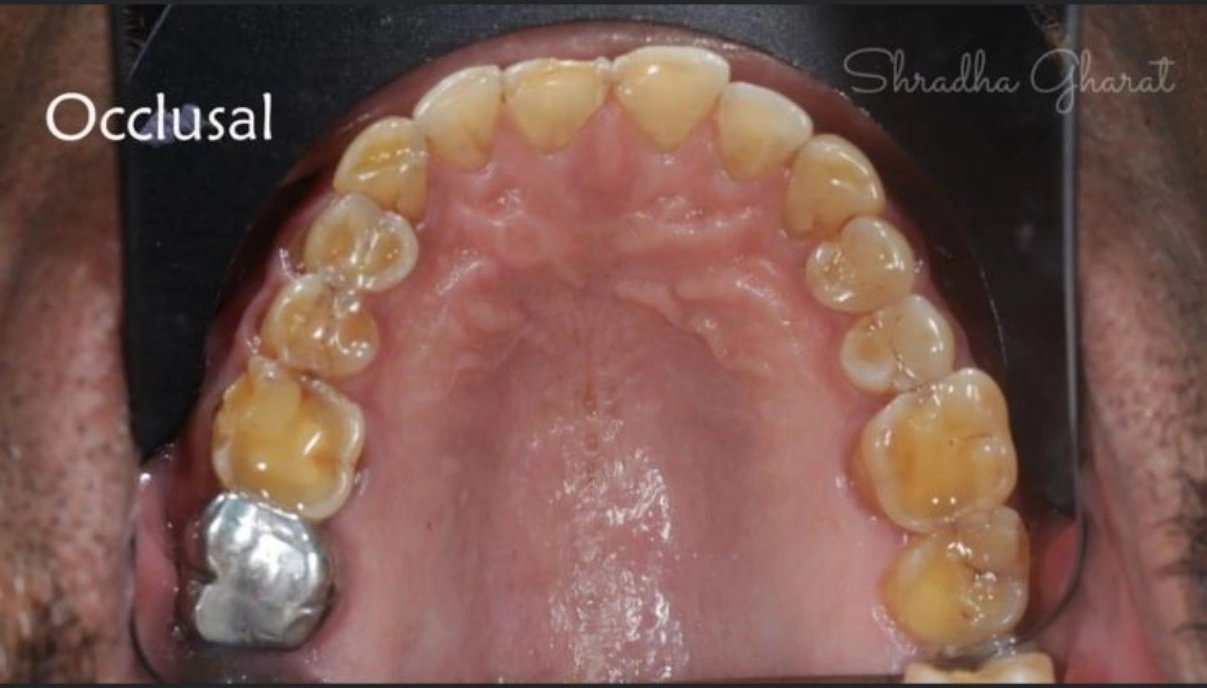

Full mouth rehabilitation includes restoration of lost tooth structure and bite. This technique sensitive procedure involves buildup of lost tooth enamel and dentin. Missing tooth can be replaced with Dental Implants or dental bridges. A Full mouth Reconstruction procedure is mainly indicated for patients with extreme tooth wear.

Full mouth rehabilitation (FMR) is a treatment plan for restoring function and function tolerance of dentition after surgery or dental restoration. It aims to restore dentition to the optimal point of function and esthetics of a healthy mouth. The treatment plan provides patients with a permanent smile that looks natural and bright.